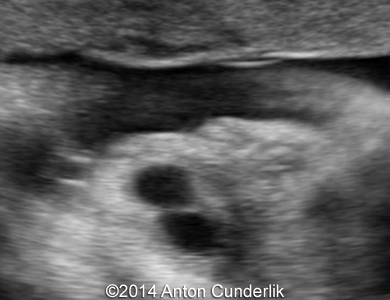

Our examination revealed a cystic, biloculate structure within fetal tongue. MRI imaging confirmed the finding. The newborn was delivered at term via cesarean section (male, 3210 g, 50 cm, Apgar score 10/10).

Image 2, 3, 4, 5, 6, 7: 30 weeks of gestation; the images show cystic structure within the fetal tongue that later turned out to be thyroglossal cyst.